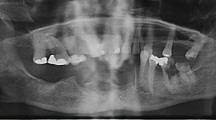

Combined ZOL and DEX therapy increases incidence of chronic wound and MRONJ in a rat model

In-vitro wound healing was mainly delayed by ZOL and ZOL(+)/DEX(+); therefore, the effect of ZOL, DEX and their combination was examined in-vivo (Fig. 2a)24. Rats were treated for 11 weeks with: ZOL, DEX, ZOL(+)/DEX(+) or saline. Rats underwent bilateral tooth extractions at week 3 and sacrifice at 11 weeks. Seven out of 50 rats died during anesthesia before or after tooth extraction. Animals that survived demonstrated normal behavior, and gained body weight. Clinically exposed bone or a fistula (MRONJ-like lesions) were evident in 50% of the ZOL(+)/DEX(+) group (20 out of 40 sites) and in 25% of the ZOL group (3 out of 12 sites; Fig. 2C). All saline (22 out of 22 sites) and DEX (12 out of 12 sites) treated rats presented complete mucosal coverage of the extraction sites (Fig. 2b).

Effect of zoledronic acid (ZOL) and dexamethasone (DEX) on wound healing in-vivo. (a) Animal study flow chart. (b) Normal healing of extraction socket (arrow) was detected in all rats in saline (control) and DEX groups. Histological slides haematoxylin and eosin demonstrated intact epithelium (ep) and wide connective tissue (ct) covering vital bone (b) that filled the extraction socket. (c) Medication-related osteonecrosis of the jaw lesions, in the ZOL(+)/DEX(+) treated rats, characterized by the presence of exposed bone (elliptical arrow). Histological slides showed incomplete epithelium (ep) with areas of non-vital bone (sequestrum, s) extending from the epithelial opening (dashed arrows) and surrounded by inflammatory infiltrate. (d) Histomorphometric analysis of area of necrosis and number of empty lacunae at the extraction site. *P ≤ 0.05 ZOL(+)/DEX(+) vs. Saline.

Histological characteristics of MRONJ were found in rats with MRONJ-like clinical lesions. Rats in the saline and DEX groups demonstrated continuous epithelium, and wide non-inflamed connective tissue, with mature vital bone filling the tooth extraction socket. ZOL(+)/DEX(+) and ZOL rats that developed MRONJ-like lesions showed epithelium discontinuation with fragments of non-vital bone surrounded by non-specific inflammatory infiltrate (Fig. 2b,c). The total area of necrotic bone and number of empty lacunae were higher in the ZOL(+)/DEX(+) compared with saline (p ≤ 0.05). The ZOL, DEX groups were similar to the saline (p > 0.05) (Fig. 2d).